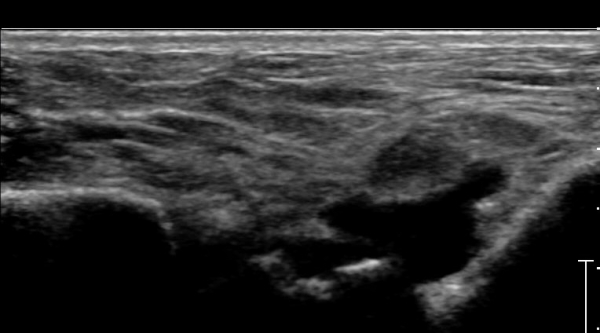

Á¾°ñºñ°ñÀδë Á¾´Ü¸é°Ë»ç¿¡¼­ °Å°ñÇϰüÀýÀÇ ¼ö¾×Àú·ù(Á¾°ñºñ°ñÀÎ´ë ½ÉºÎ ¼ö¾×Àú·ù)°¡

°üÂûµÈ´Ù(»çÁø 4).